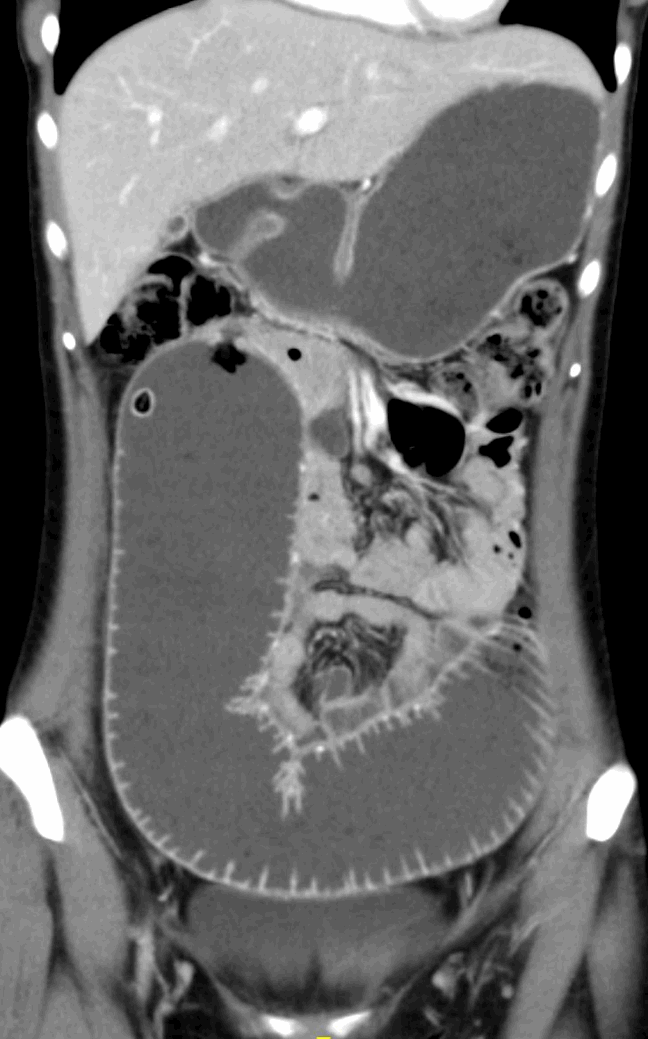

A 28-year-old female with a past medical history of intestinal tuberculosis (TB) and chronic constipation presents with worsening constipation for one year. In 2009 she was diagnosed with tuberculosis based on symptoms of fevers, chills, nausea, and chronic abdominal pain. She was treated with isoniazid, pyrazinamide and ethambutol for approximately 1 year, her imaging at the time of diagnosis was negative for pulmonary disease, but positive for multiple intestinal strictures. After completion of therapy, she had improvement in her strictures on imaging, but continued to have intermittent episodes of severe abdominal pain, bloating, anorexia, nausea, and constipation if any significant amount of fiber was ingested. This was managed on a low residue diet and daily lactulose for about 10 years. In 2018 she presented to our clinic. A computed tomography (CT) scan was obtained (Figure 1) demonstrating a transition point in the mid jejunum with dilation of her small intestine proximally. She was taken to the operating room, where she was found to have a single mid-jejunal stricture with two proximal scybala creating a ball-valve mechanism (Figure 2). She received a segmental resection, primary anastomosis and biopsy of mesenteric lymph node. The specimens were sent for pathology and culture, which were negative for tuberculosis. H&E staining of the resected specimen demonstrated gastric heterotopia with antral type mucosa devoid of other gastric mucosal subtypes (Figure 3). Mesenteric lymph nodes were without active TB and showed reactive follicular hyperplasia without granulomas, consistent with a prior TB infection. QuantiFERON gold test was positive, but a chest x-ray was negative for active TB.

Figure 1. Preoperative Computed Tomography (CT) Abdomen Pelvis with Contrast. A chronically distended proximal jejunum with a narrowed lumen visible in the RUQ at the lateral edge of the dilated jejunum

Figure 1. Preoperative Computed Tomography (CT) Abdomen Pelvis with Contrast. A chronically distended proximal jejunum with a narrowed lumen visible in the RUQ at the lateral edge of the dilated jejunum.